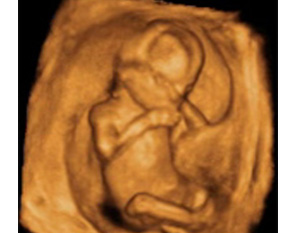

Embarazo semana 15: El bebé crece y dobla su peso

La semana 15 de embarazo es un hito en el desarrollo del bebé: dobla su peso en una semana, empieza el proceso de osificación de los huesos, y lo más emocionante de todo, algunas mamás ya pueden sentir a su hijo dentro del útero materno. El pequeño se recubre un pelo muy fino denominado lanugo.

En la semana 15 de gestación, el feto mide entre 9 y 10 centímetros y pesa unos 50 gramos, el doble que la semana anterior.

Una capa fina de pelo llamada lanugo recubre la gran parte del cuerpo del bebé. Su piel es muy fina y a través de ella se podrían ver los vasos sanguíneos que circulan por debajo.

Los ojos siguen separados aunque cada vez se acercan más a la raíz nasal. En las orejas se distinguen los distintos pliegues que las componen. La barbilla se empieza despegar del tórax.

En lo referente a los huesos, comienza el proceso de osificación en el feto: cada vez son más fuertes, ya que retienen más calcio.